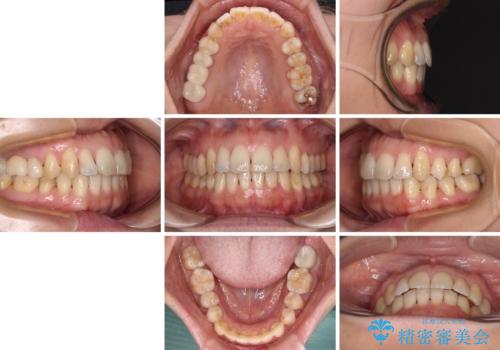

- 上下奥歯の欠損を気にして来院された患者様です。

以前矯正した後戻りにより前歯に叢生が認められたため、矯正治療の提案をしたところ、補綴治療と合わせて矯正治療を行うこととしました。

下顎欠損部はインプラントにて、上顎中間欠損部はブリッジによる補綴治療を行い、他にも気になっている銀歯をセラミックインレーやゴールドインレーにて修復治療を行うこととしました。

後戻りの程度は軽度であったため、インビザライン・ライトを用いて歯列を整えました。

再度後戻りするリスクを最小限に食い止めるため、下顎前歯の舌側を細いワイヤーで固定しました。